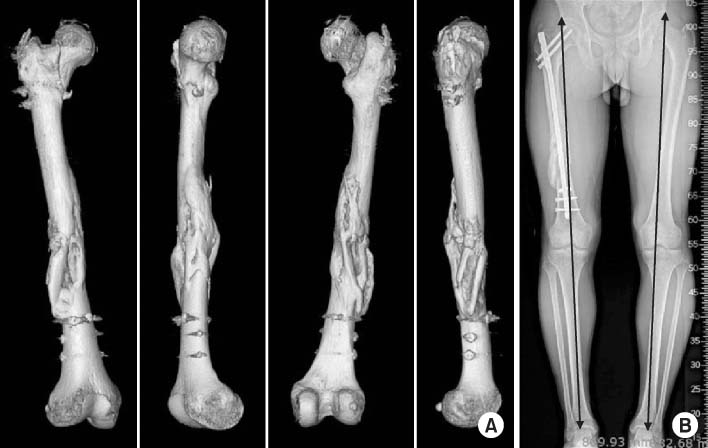

Fig. 2

A 20-year-old male was poly-traumatized after a traffic accident. (A) Anteroposterior radiograph shows an irregular complex femur shaft fracture with a non-displaced fracture of the ipsilateral femoral neck. (B) He underwent damage control-external fixator application at the time of brain surgery in the neurosurgery department. (C) After 3-weeks, he underwent antegrade nailing with two Poller screws after closed reduction with preservation of fracture site biology. Serial radiographs (D: initial postoperative, E: postoperative 2 month, F: postoperative 4 months) show bridging callus progression until radiologic healing.

Fig. 3

(A) Three-dimensional-reconstructed computed tomography images at postoperative 5 months show full consolidation of a complex femur shaft fracture including neck fracture component. (B) However standing lower extremity scanogram shows a limb length discrepancy of 15 mm.

Fig. 2 A 20-year-old male was poly-traumatized after a traffic accident. (A) Anteroposterior radiograph shows an irregular complex femur shaft fracture with a non-displaced fracture of the ipsilateral femoral neck. (B) He underwent damage control-external fixator application at the time of brain surgery in the neurosurgery department. (C) After 3-weeks, he underwent antegrade nailing with two Poller screws after closed reduction with preservation of fracture site biology. Serial radiographs (D: initial postoperative, E: postoperative 2 month, F: postoperative 4 months) show bridging callus progression until radiologic healing.

Fig. 3 (A) Three-dimensional-reconstructed computed tomography images at postoperative 5 months show full consolidation of a complex femur shaft fracture including neck fracture component. (B) However standing lower extremity scanogram shows a limb length discrepancy of 15 mm.